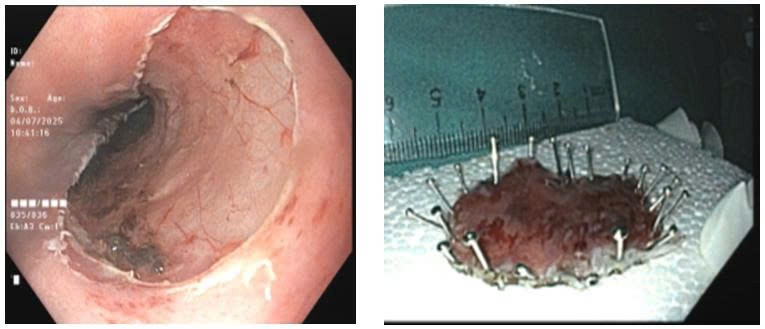

Hình ảnh tổn thương ung thư sớm thực quản trên nội soi.

Kết quả nội soi phát hiện tại thực quản cách cung răng trên từ 30cm đến 36cm có tổn thương thay đổi màu sắc kích thước khoảng 2cm x 5.5cm.

Dưới phân tích của kỹ thuật nội soi phóng đại và nhuộm màu ảo (NBI) tổn thương có đặc điểm vi cấu trúc mạch máu biến đổi phù hợp với một tổn thương ung thư sớm. Các bác sĩ đã tiến hành sinh thiết tổn thương gửi làm giải phẫu bệnh, kết quả loạn sản độ cao.

Tổn thương ung thư sớm thực quản được cắt bỏ qua nội soi - Ảnh BVCC

Đánh giá tổn thương tiền ung thư rất lớn với kích thước chiều dài trên 5cm, BSCKI Nguyễn Quảng Đại, Trưởng Khoa Nội tiêu hóa, Bệnh viện Bãi Cháy với kinh nghiệm dày dạn trong can thiệp ung thư sớm đã cùng ê-kíp nội soi phối hợp nhuần nhuyễn, cắt bỏ hoàn toàn tổn thương tiền ung thư ra khỏi thực quản của bệnh nhân qua nội soi bằng phương pháp cắt tách dưới niêm mạc ESD.

Khối bệnh phẩm tiếp tục được gửi đi làm giải phẫu bệnh, kết quả diện cắt đáy và diện cắt bên không còn u. Sau can thiệp, người bệnh ổn định, được xuất viện trở về với cuộc sống bình thường sau 5 ngày.